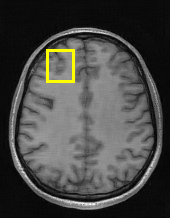

Edge preserving has always been a crucial concern in the design of reconstruction models. To improve the quality of reconstructed images and preserve image edges, some works suggested introducing edge priors in the original restoration problem to preserve image edges [4, 34]. However, they will suffer from complicated algorithm design and time-consuming training processes. Recently, some more efficient methods have been proposed to use edge maps as external guidance for image restoration. For example, Yang et al. [48] used off-the-shelf edge detectors to extract image edges from the degraded images. Fang et al. [12] predicted image edges by constructing an edge reconstruction network. Huang et al. [18] designed a novel dual discriminator GAN framework for solving fast multi-channel MRI, in which one GAN network is built for edge information enhancement. Inspired by these methods, we also consider introducing image edge prior as external guidance to MRI reconstruction since 1) image edges are prominent and distinguishable features in MRI (see Fig. 1), which can serve as a good guide to the model to recover high-frequency details; 2) the ground truth edges can be easily fetched via ordinary edge extraction operators, like Canny, Sobel, and Prewitt, which means that the edge maps can be learned in a data-driven manner. However, how to effectively utilize image edge priors to guide image reconstruction still remains a challenge. In some methods, edge information was simply concatenated with the input image and passed to the next stages. Though this is a simple way to utilize the edge priors, it may not give full play to the guiding role of the edge priors. Therefore, in this work, we want to explore a more efficient and effective mechanism to fully take advantage of image edge priors.

(a)

(b)

(c)

fastMRI is a large-scale MR dataset jointly established by Facebook AI Research and NYU Langone Health. It provides both knee and brain datasets for evaluation. In our work, we use the multi-coil knee dataset, which was acquired on three clinical 3T systems or one clinical 1.5T system using a 15-channel knee coil array. The dataset includes data from two pulse sequences, yielding coronal proton-density weighting with (PDFS) and without (PD) fat suppression. As is shown in Fig. 1, PD images usually contain more structural and prominent edge features than PDFS images, which suggests that it is more challenging to use edge guidance on PDFS datasets. Therefore, we explore the effectiveness of EAMRI on these two modalities. Following [13], for both PD and PDFS knee datasets, we separately filter out 227 volumes (8332 slices) for training and 24 volumes (1665 slices) for testing. The dataset is centrally cropped to .